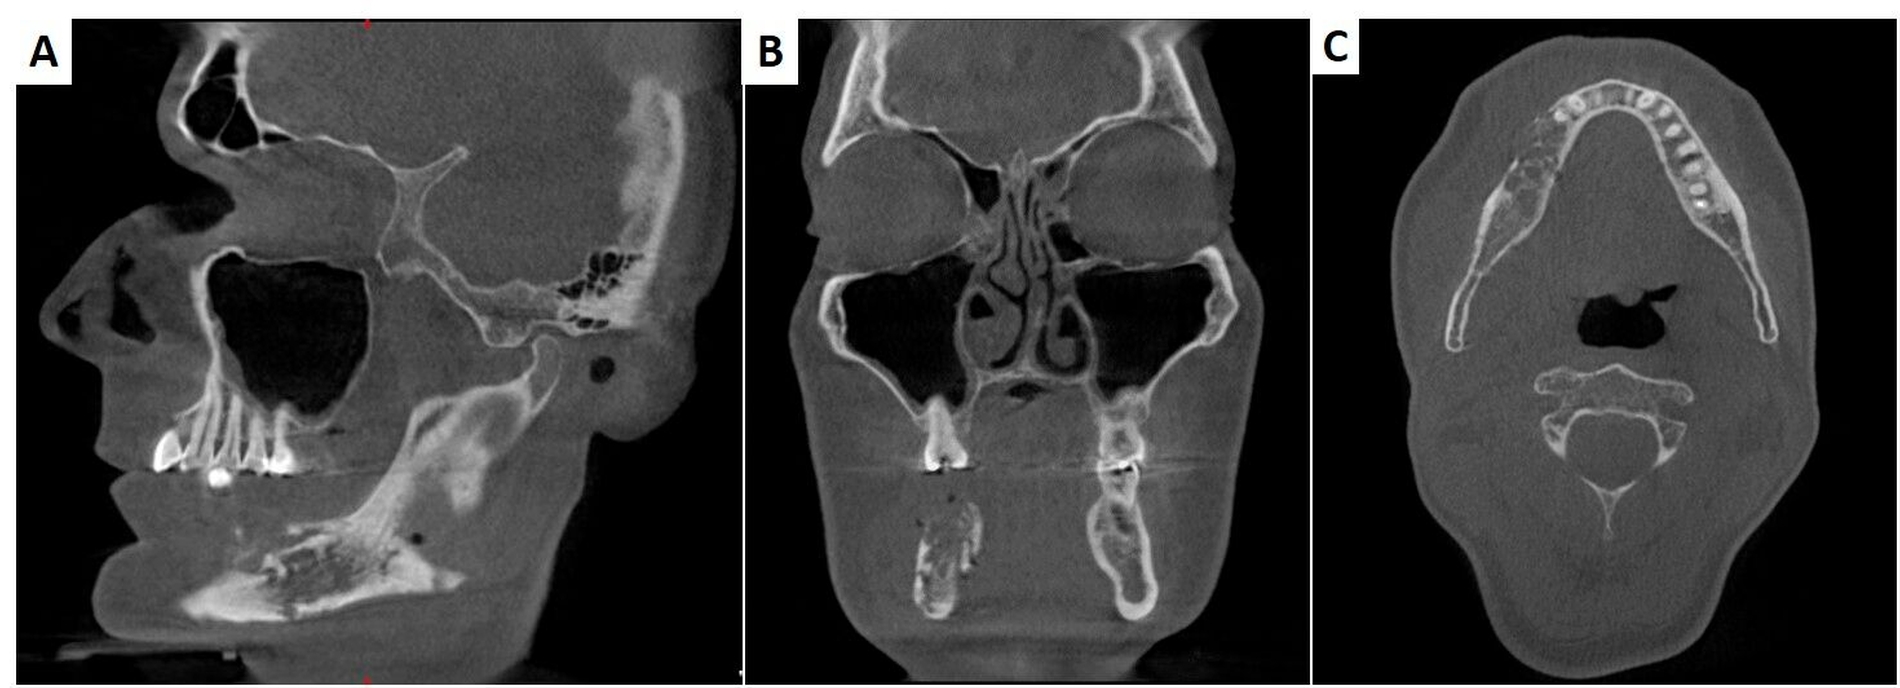

Radiologisch ließ sich eine ausgedehnte Knochendestruktion mit Sequesterbildung und Periostreaktion im vierten Quadranten nachweisen (Abbildung 3). Gemeinsam mit dem Patienten und insbesondere unter Berücksichtigung seiner extremen psychischen Belastung wurde anschließend die Entscheidung zur Dekortikation mit dem Versuch des Erhalts der Unterkieferkontinuität getroffen, wobei bei dem ausgeprägten klinischen Bild von ärztlicher Seite eine Kontinuitätsresektion unter Erhalt des Nervus alveolaris inferior in Kombination mit einer mikrovaskulären Rekonstruktion empfohlen wurde.

Die Operation konnte am Folgetag komplikationslos in Intubationsnarkose durchgeführt werden. Bei ausreichender Reststabilität des Unterkiefers wurde auf eine osteosynthetische Versorgung verzichtet (Abbildung 4). Die histopathologische Nachuntersuchung der intraoperativ gesammelten Knochenproben bestätigte die Verdachtsdiagnose einer sekundär chronischen Osteomyelitis. Es zeigten sich eine chronisch granulierende Entzündung der Schleimhaut sowie eine floride granulozytäre Infiltration der Markräume des erfassten kompakten Knochengewebes.

Typischerweise präsentiert sich die sekundär chronische Osteomyelitis mit dumpfen Schmerzen und einer derben Schwellung, die auf die ausgeprägte periostale Knochenreaktion zurückzuführen ist. Diese charakteristische Periostreaktion lässt sich ebenfalls radiologisch nachweisen. Im DVT oder CT zeigen sich bildmorphologisch Knochendestruktionen neben Sequestern und Sklerosierungen sowie Periostschwielen. Ein weiteres diagnostisches Hilfsmittel ist die Magnetresonanztomografie, womit sich die Ausdehnung der Entzündung im Knochenmark gut darstellen lässt. Im T2-gewichteten Bild zeigt der von einer Osteomyelitis betroffene Knochen, bedingt durch das Markraumödem, eine Zunahme der Signalintensität, während im Gewebe eine durch die erhöhte Gefäßpermeabilität gesteigerte Kontrastmittelanreicherung zu sehen ist [Schuknecht et al., 1997; Schuknecht und Valavanis, 2003]. Die Ausbreitung der Entzündung findet entlang des neurovaskulären Bündels statt und die damit einhergehende Nerv-Irritation führt zur Hypästhesie im Versorgungsgebiet des Nervus alveolaris inferior, dem sogenannten Vincent-Symptom [Dym und Zeidan, 2017].